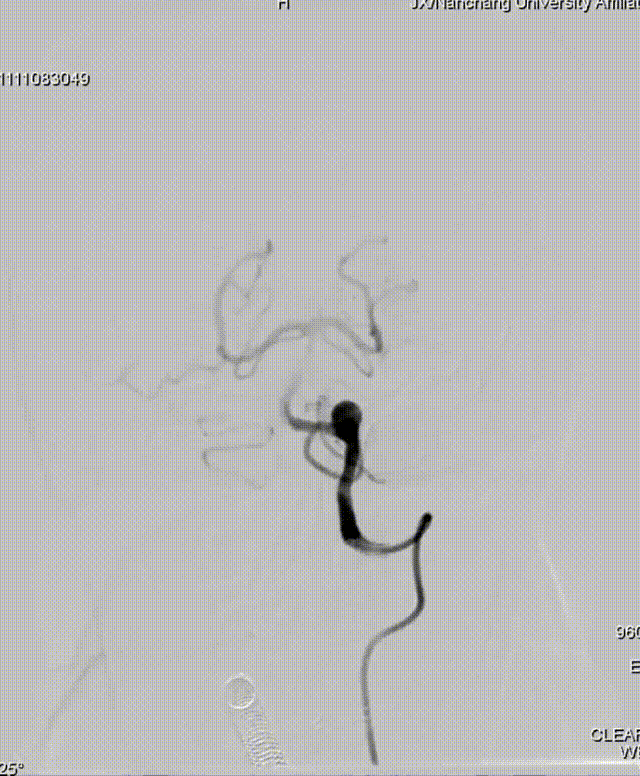

Tubridge Plus Case 2